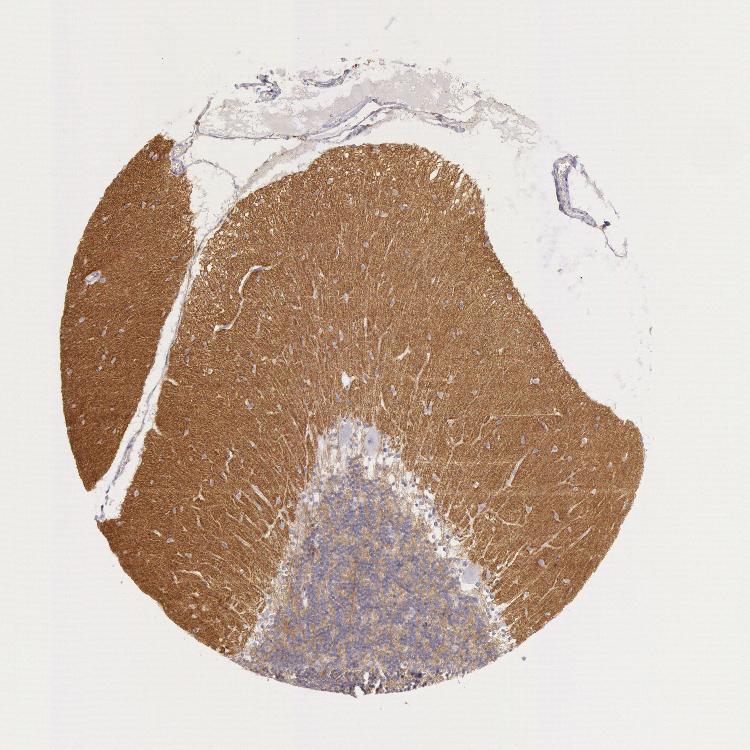

BRAIN CEREBELLUM Show tissue menu

CEREBELLUM - Expression summary

CEREBELLUM - Antibody stainingi

Antibody staining in the annotated cell types in the current human tissue is reported as not detected, low, medium, or high, based on conventional immunohistochemistry profiling in selected tissues. This score is based on the combination of the staining intensity and fraction of stained cells.

Each image is clickable and will lead to virtual microscopy that enables deeper exploration of all samples and also displays staining intensity scores, fraction scores and subcellular localization as well as patient and tissue information for each sample.

Antibody HPA001231Antibody CAB004492

Purkinje cells Not detectedNot detected

Cells in granular layer LowLow

Cells in molecular layer Not detectedNot detected